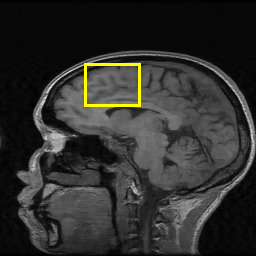

Edge preserving has always been a crucial concern in the design of reconstruction models. To improve the quality of reconstructed images and preserve image edges, some works suggested introducing edge priors in the original restoration problem to preserve image edges [4, 34]. However, they will suffer from complicated algorithm design and time-consuming training processes. Recently, some more efficient methods have been proposed to use edge maps as external guidance for image restoration. For example, Yang et al. [48] used off-the-shelf edge detectors to extract image edges from the degraded images. Fang et al. [12] predicted image edges by constructing an edge reconstruction network. Huang et al. [18] designed a novel dual discriminator GAN framework for solving fast multi-channel MRI, in which one GAN network is built for edge information enhancement. Inspired by these methods, we also consider introducing image edge prior as external guidance to MRI reconstruction since 1) image edges are prominent and distinguishable features in MRI (see Fig. 1), which can serve as a good guide to the model to recover high-frequency details; 2) the ground truth edges can be easily fetched via ordinary edge extraction operators, like Canny, Sobel, and Prewitt, which means that the edge maps can be learned in a data-driven manner. However, how to effectively utilize image edge priors to guide image reconstruction still remains a challenge. In some methods, edge information was simply concatenated with the input image and passed to the next stages. Though this is a simple way to utilize the edge priors, it may not give full play to the guiding role of the edge priors. Therefore, in this work, we want to explore a more efficient and effective mechanism to fully take advantage of image edge priors.

(a)

(b)

(c)

fastMRI is a large-scale MR dataset jointly established by Facebook AI Research and NYU Langone Health. It provides both knee and brain datasets for evaluation. In our work, we use the multi-coil knee dataset, which was acquired on three clinical 3T systems or one clinical 1.5T system using a 15-channel knee coil array. The dataset includes data from two pulse sequences, yielding coronal proton-density weighting with (PDFS) and without (PD) fat suppression. As is shown in Fig. 1, PD images usually contain more structural and prominent edge features than PDFS images, which suggests that it is more challenging to use edge guidance on PDFS datasets. Therefore, we explore the effectiveness of EAMRI on these two modalities. Following [13], for both PD and PDFS knee datasets, we separately filter out 227 volumes (8332 slices) for training and 24 volumes (1665 slices) for testing. The dataset is centrally cropped to .